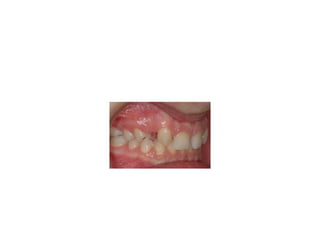

pre-op